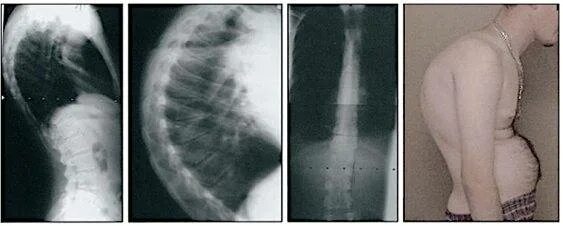

Болезнь шейермана мау что